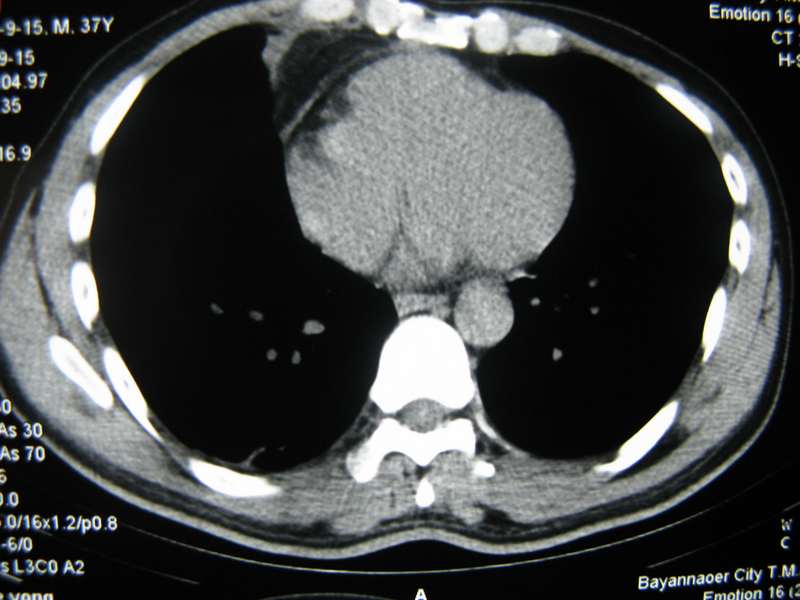

男,37岁,主述胸疼厉害,无咳嗽,无发热,血象也不高,病灶内ct值脂肪密度,右侧胸腔内少量积液,同道们考虑什么?谢谢!

脂肪垫,右下肺感染,少许积液是症状所在

纵膈脂肪堆积,右肺慢性炎症。

两肺下叶基底段纤维灶,右肺下叶基底背侧相应胸膜肥厚,右肺中叶内侧段部分不张。前中下纵隔团块状脂肪影,随访除外胸腺脂肪瘤。

不除外膈疝。